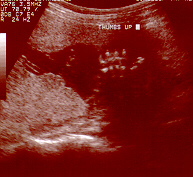

Thumb's Up

Jolie gives her Thumbs Up!